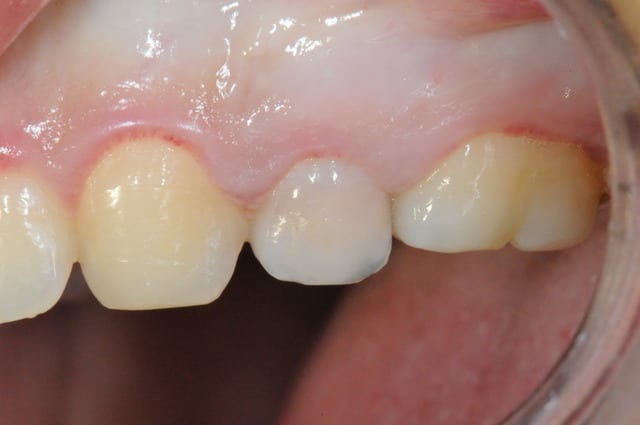

ne jamais faire une jolie provisoire

comme ça la prothèse conventionelle est zolie...

mis à part le liseret gris du collet suis content du résultat et pourtant c'était pas gagné d'avance : pas de GA ou peu et nécessité de faire une rog

donc la EII et ROG (nanobone + collagene +prf)

pas de MCI

à la réouverture déplacement en vestibulaire de la GA palatine pour redonner du "volume"

fouilla content il en faut peu pour être heureux..